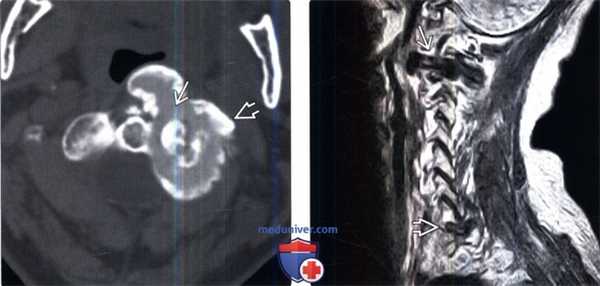

(Слева) Аксиальный КТ-срез: четко ограниченное кальцифицированное образование, расположенное на уровне левого дугоот-ростчатого сустава С1-С2 и представляющее собой крупное, гомогенное, достаточно плотное внутри образование Я, ограниченное еще более плотной стенкой.

(Справа) На сагиттальном Т1-ВИ определяется низкоинтенсивное образование, которое по данным КТ оказалось кальцинатом. Второй небольшой очаг опухолевого кальциноза виден на уровне С7-Т1. МР-признаки ОК достаточно неспецифичны, для подтверждения диагноза показана КТ.